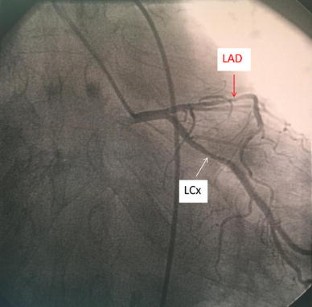

Fractional flow reserve (FFR) is a standardized and well-established method frequently used in clinical practice to evaluate the hemodynamic significance of epicardial coronary stenosis identified by coronary angiography. It is based on the change in the pressure gradient across the stenosis after the achievement of maximal hyperemia of the coronary circulation which is commonly induced by intravenous (IV) or intracoronary (IC) administration of adenosine. Here, we have described three cases of IC adenosine-induced ventricular arrhythmias during FFR measurement from our institution, and after literature review we found that all the cases of ventricular arrhythmias induced by adenosine during FFR measurement were observed where it was administered via IC route. Although a causal relationship between the use of IC adenosine during FFR measurement and the induction of ventricular arrhythmias is not yet established, we suggest using IV adenosine as the preferred route of administration until we better understand the incidence and mechanism underlying this phenomenon.

Raffaele P, Tullio N, Giuseppe G, et al. Adenosine-induced torsade de pointes complicating a fractional flow reserve measurement in a right coronary artery intermediate stenosis. Cardiovasc Revascularization Med. 2013;14:118–20.

Shah AH, Chan W, Seidelin PH. Ventricular fibrillation precipitated by intracoronary adenosine during fractional flow reserve assessment: a cautionary tale. Heart Lung Circ. 2015;11:e173–5.